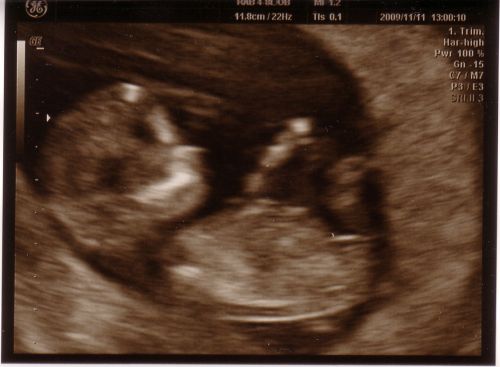

Töltök fel egy képet Ödönkéről(Párom így hívja,pedig nem is így fogják hívni! :D )!Olyan édes volt,szopizta az újját is!

És akkor az adatok:

CRL:56mm

BPD:22mm

NT:1,7mm

Orrcsont látható,ritmusos szívműködés,gerinc még nem megitélhető :oops: ,hasfal zárt,gyomorban,hólyagban folyadék,látható alsó és felső végtagok!

És az uh-os doki szerint 12hét+1napos voltam szerdán,én szerintem pedig 12hét+4napos voltam!És ebben én biztos vagyok!!Szerintetek,hogy a gerincet még nem látta,az baj??